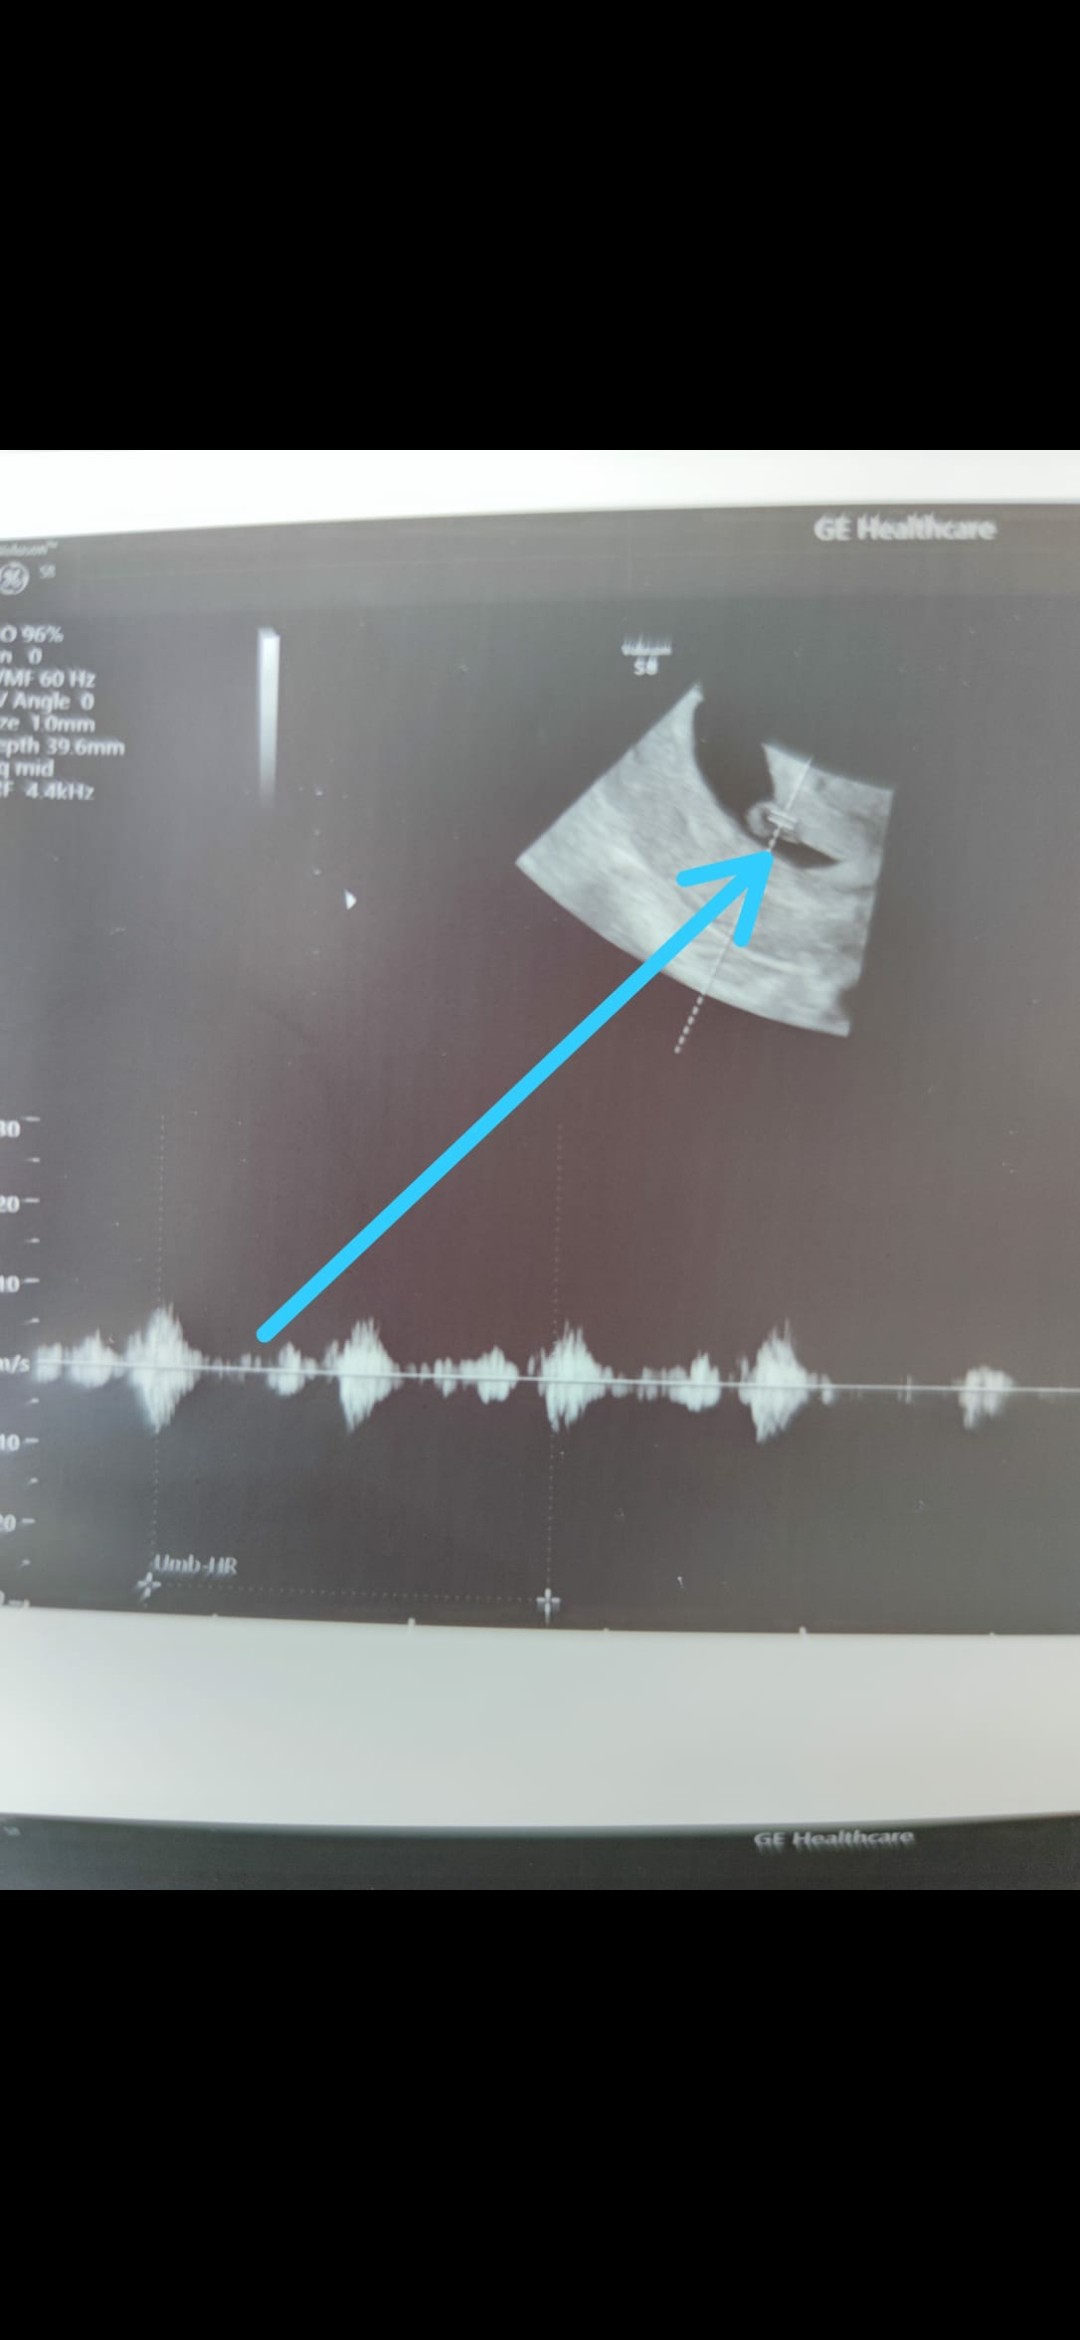

Już po wizycie! Jest zarodek i jest serduszko! ❤️

Screenshot_2021-05-25-13-21-30-028_com.whatsapp.jpg